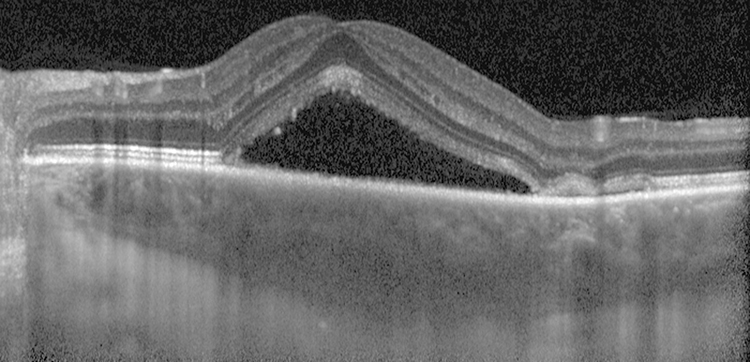

OCT is helpful in demonstrating SRF or PEDs and for monitoring purposes. Enhanced-depth imaging OCT often demonstrates choroidal thickening and may be a useful adjunct in diagnosis (See Figures 11.15.2 and 11.15.3).